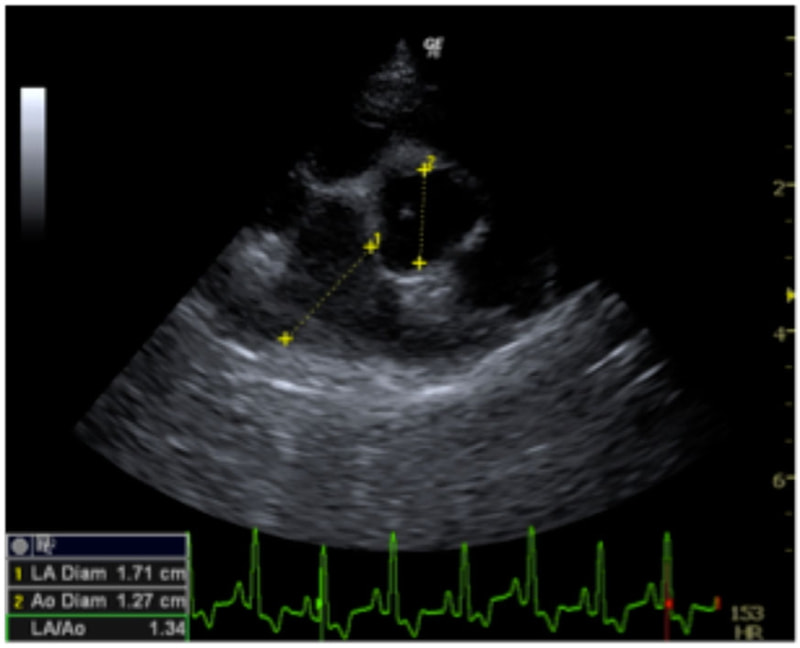

D:La/Ao比の重度拡大あり

左側胸壁心尖部領域を最強点とするLevine 5/6の収縮期性心雑音が聴取された。安静時にも咳が認められる。胸部レントゲン検査において重度の心拡大が及び肺水腫が認められた。超音波検査では、重度の僧帽弁閉鎖不全、三尖弁閉鎖不全が認められた。三尖弁逆流速度から肺高血圧症が示唆された。ACE阻害薬、ピモベンダン、硝酸イソソルビド徐放剤、ベラプロストナトリウム、利尿剤としてフロセミド及びスピロノラクトンを用いて治療を行っている。